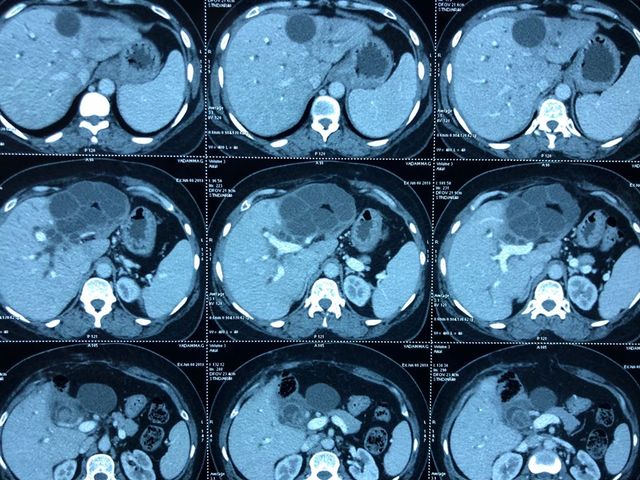

Challenging emergency during the COVID: Child’s A CLD with HUGE gastric varices uncontrolled

Child’s A CLD with HUGE gastric varices uncontrolled by Endoscopic glue and attempted EUS coiling. One salvage option would be TIPSS with balloon vascular occlusion but due to logistics we went for modified sugiura procedure. Splenectomy + Gastro esophageal devascularisation with anterior Gastrotomy and overseeing of gastric varices with pyloroplasty. Images show 1 CECT showing large gastric fundal varices. 2,3,4 Gastro Esophageal devasc 5, 6 Large fundal varices before and after oversewing. 7. Anterior gastrotomy 8. Pyloroplasty. Postoperative recovery was uneventful.